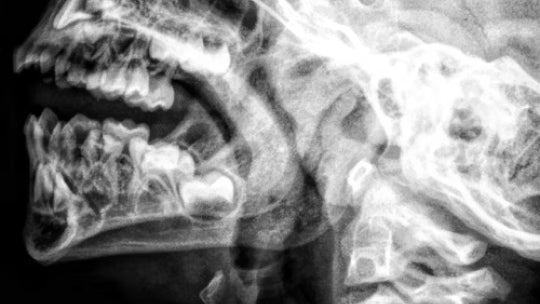

Photobiomodulation with simultaneous use of red and infrared light emitting diodes in the treatment of temporomandibular disorder: study protocol for a randomized, controlled and double-blind clinical trial.

Description: This is a study protocol for a randomized, controlled, and double-blind clinical trial designed

to evaluate the effects of photobiomodulation using simultaneous red and infrared LEDs on pain,

mandibular range of motion, and the electrical activity of masticatory muscles in individuals with

Temporomandibular Disorder (TMD).